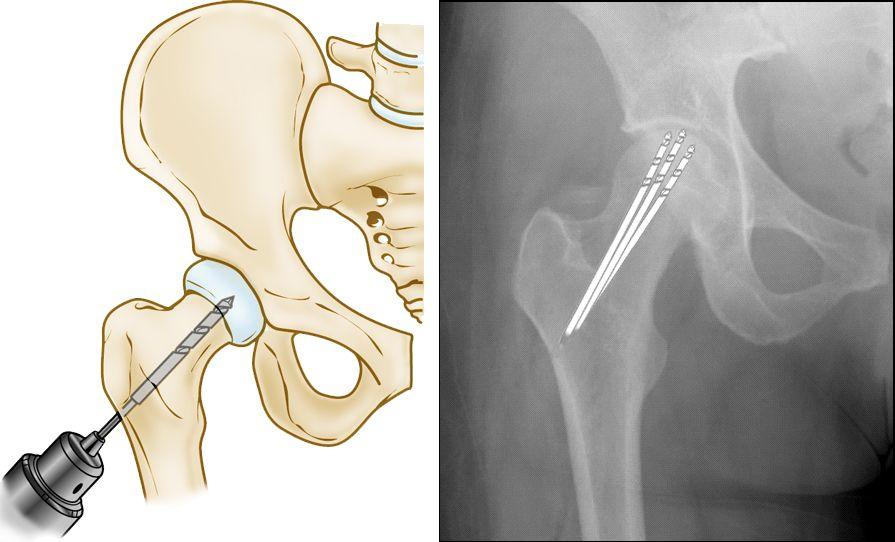

核心减压

该手术包括在股骨头上钻一个或几个较小的孔,以减轻骨骼压力,并为新血管创建通道以滋养髋部受影响的区域。

当髋关节骨坏死被及早诊断出来时,核心减压有时可以成功预防股骨头塌陷和关节炎的发展。

(左)核心减压示意图。(右)在此 X 射线中,钻孔线显示了手术中使用的小钻孔的路径。